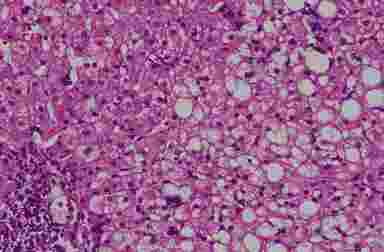

Морфология. Жировая дистрофия (стеатоз печени).  Жировые включения локализуются преимущественно в гепатоцитах 2 и 3 зон печеночного ацинуса, в более тяжелых случаях капли жира распределяются в ткани печени диффузно (рис. 6.1). В большинстве случаев включения имеют крупные размеры (крупнокапельное ожирение или макровезикулярный стеатоз). Микровезикулярный стеатоз (мелкокапельное ожирение) ассоциирован с повреждением митохондрий, поэтому наблюдается уменьшение количества митохондриальной ДНК в гепатоцитах.

Жировой гепатоз

Рис. 6.1. Жировой гепатоз (биоптат печени, окраска г/э, х200). Диффузная крупнокапельная дистрофия гепатоцитов